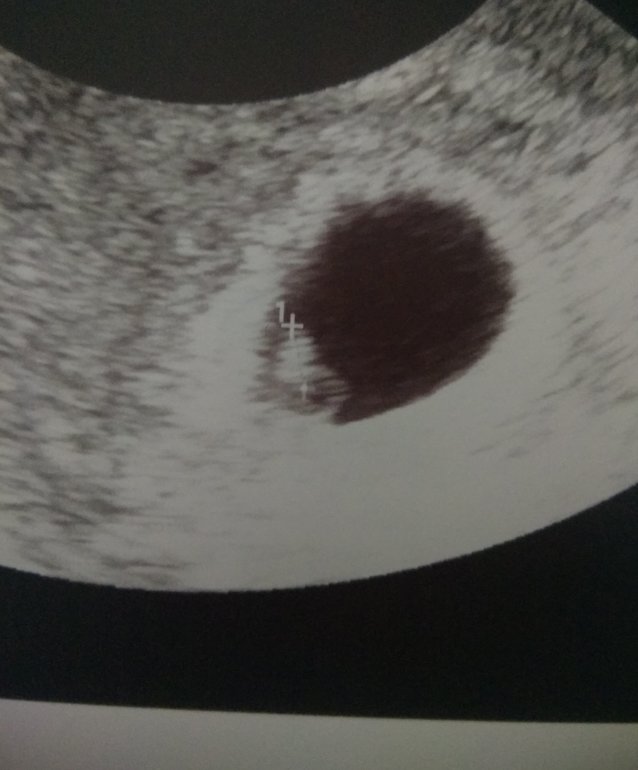

Наше первое УЗИ )

Девули , ну вот и состоялось наше первое УЗИ )))

Малышуля там где надо ))) !!! Сердечко сразу услышали и дали послушать - 163 уд.)))

А вот наша первая фотография )))